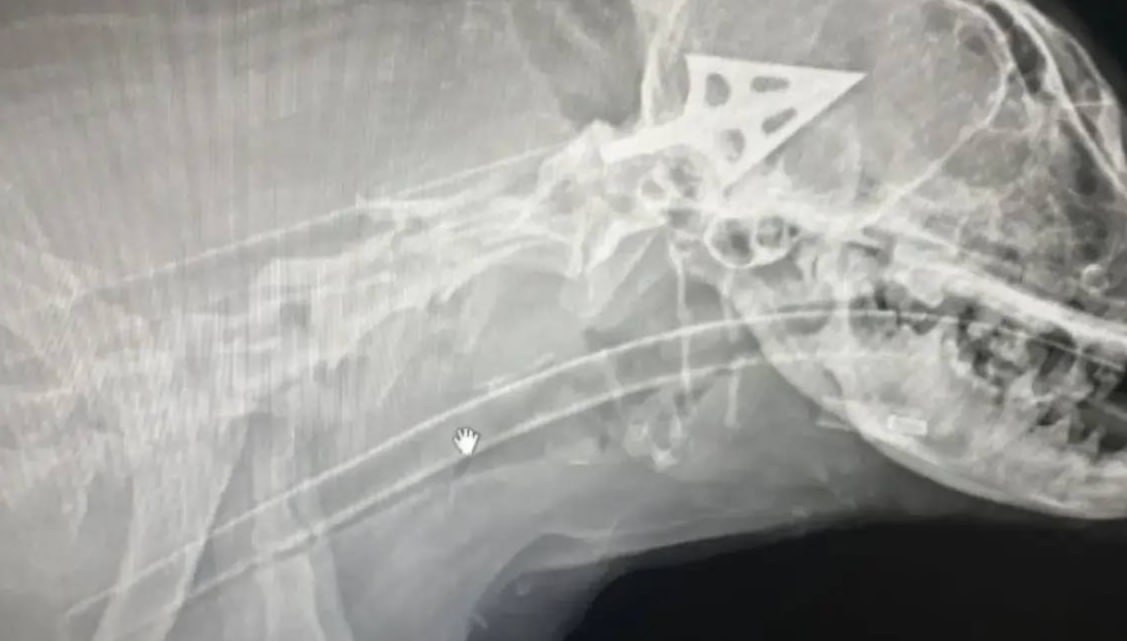

Стрелой ранили собаку в Новороссийске.

Такое сообщение опубликовали в соцсетях. Якобы в одном из районов города-героя волонтеры обнаружили пострадавшее животное.